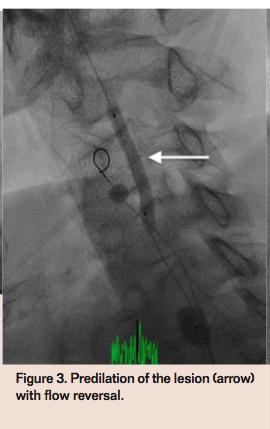

The patient was brought to the angiography suite for elective carotid artery stenting in the setting of recurrent embolic events. Vascular access was obtained in the right common femoral artery with a 10 Fr sheath and the right femoral vein with a 6 Fr sheath. A 6 Fr internal mammary diagnostic catheter was used to selectively engage the left common carotid artery (CCA) and diagnostic angiogram revealed a 90% ulcerated stenosis in the proximal left ICA (Figure 1) with preserved intracerebral flow. A stiff angled glidewire (Terumo) was advanced into the left external carotid artery (ECA) to allow exchange for the 9.5 Fr CCA balloon sheath (Gore) into the left CCA through the 10 Fr arterial sheath. An ECA balloon wire (Gore) was then positioned at the ostium of the left ECA. Carotid flow reversal was initiated after inflation of the CCA and ECA balloons (Figure 2) with retrograde flow through the left ICA and CCA and continuous flow through the external filter into the venous system via the 6 Fr venous sheath. A Prowater guidewire (Abbott Vascular) was advanced through the left ICA lesion into the distal segment of the artery. A Viatrac 4 mm x 30 mm balloon (Abbott Vascular) was used to predilate the lesion

with good expansion